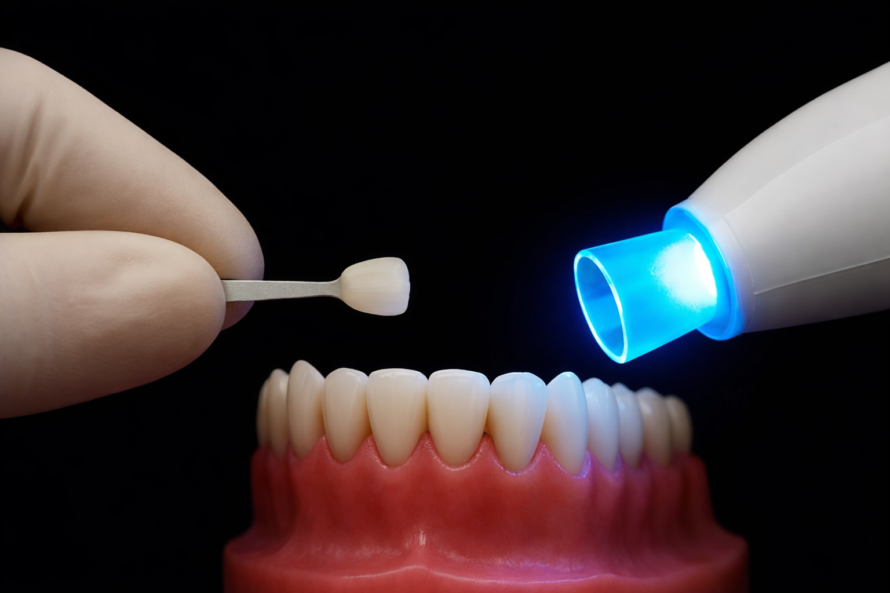

Facettes dentaires

Les facettes dentaires sont la solution idéale pour transformer votre sourire rapidement. Grâce à des facettes fines et esthétiques, nous corrigeons la forme, la couleur et l’alignement des dents visibles. Un résultat naturel, éclatant et parfaitement adapté à votre visage.